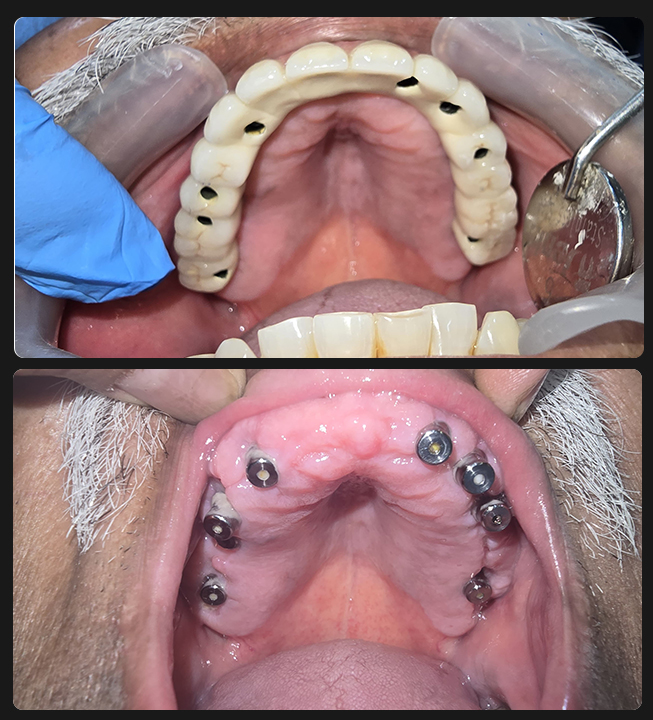

Full Mouth Implants with all Ceramic Crowns

Mr. Ramnani (Florida, USA)